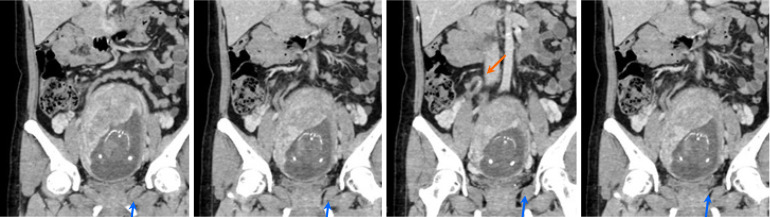

Results: Idiopathic pain was the most common diagnosis (104 cases, 45.2%), followed by appendicitis (46 cases, 20.0%) and diverticulitis (27 cases, 11.7%). Right lower quadrant pain predominantly revealed appendicitis (20.2%), whereas left lower quadrant pain frequently indicated diverticulitis (12.1%). Nonspecific pain cases have diverse etiologies. Rare conditions included situs inversus (one case) and intestinal malrotation (one case). Pregnancy-related diagnoses included acute appendicitis and uterine fibroid degeneration.